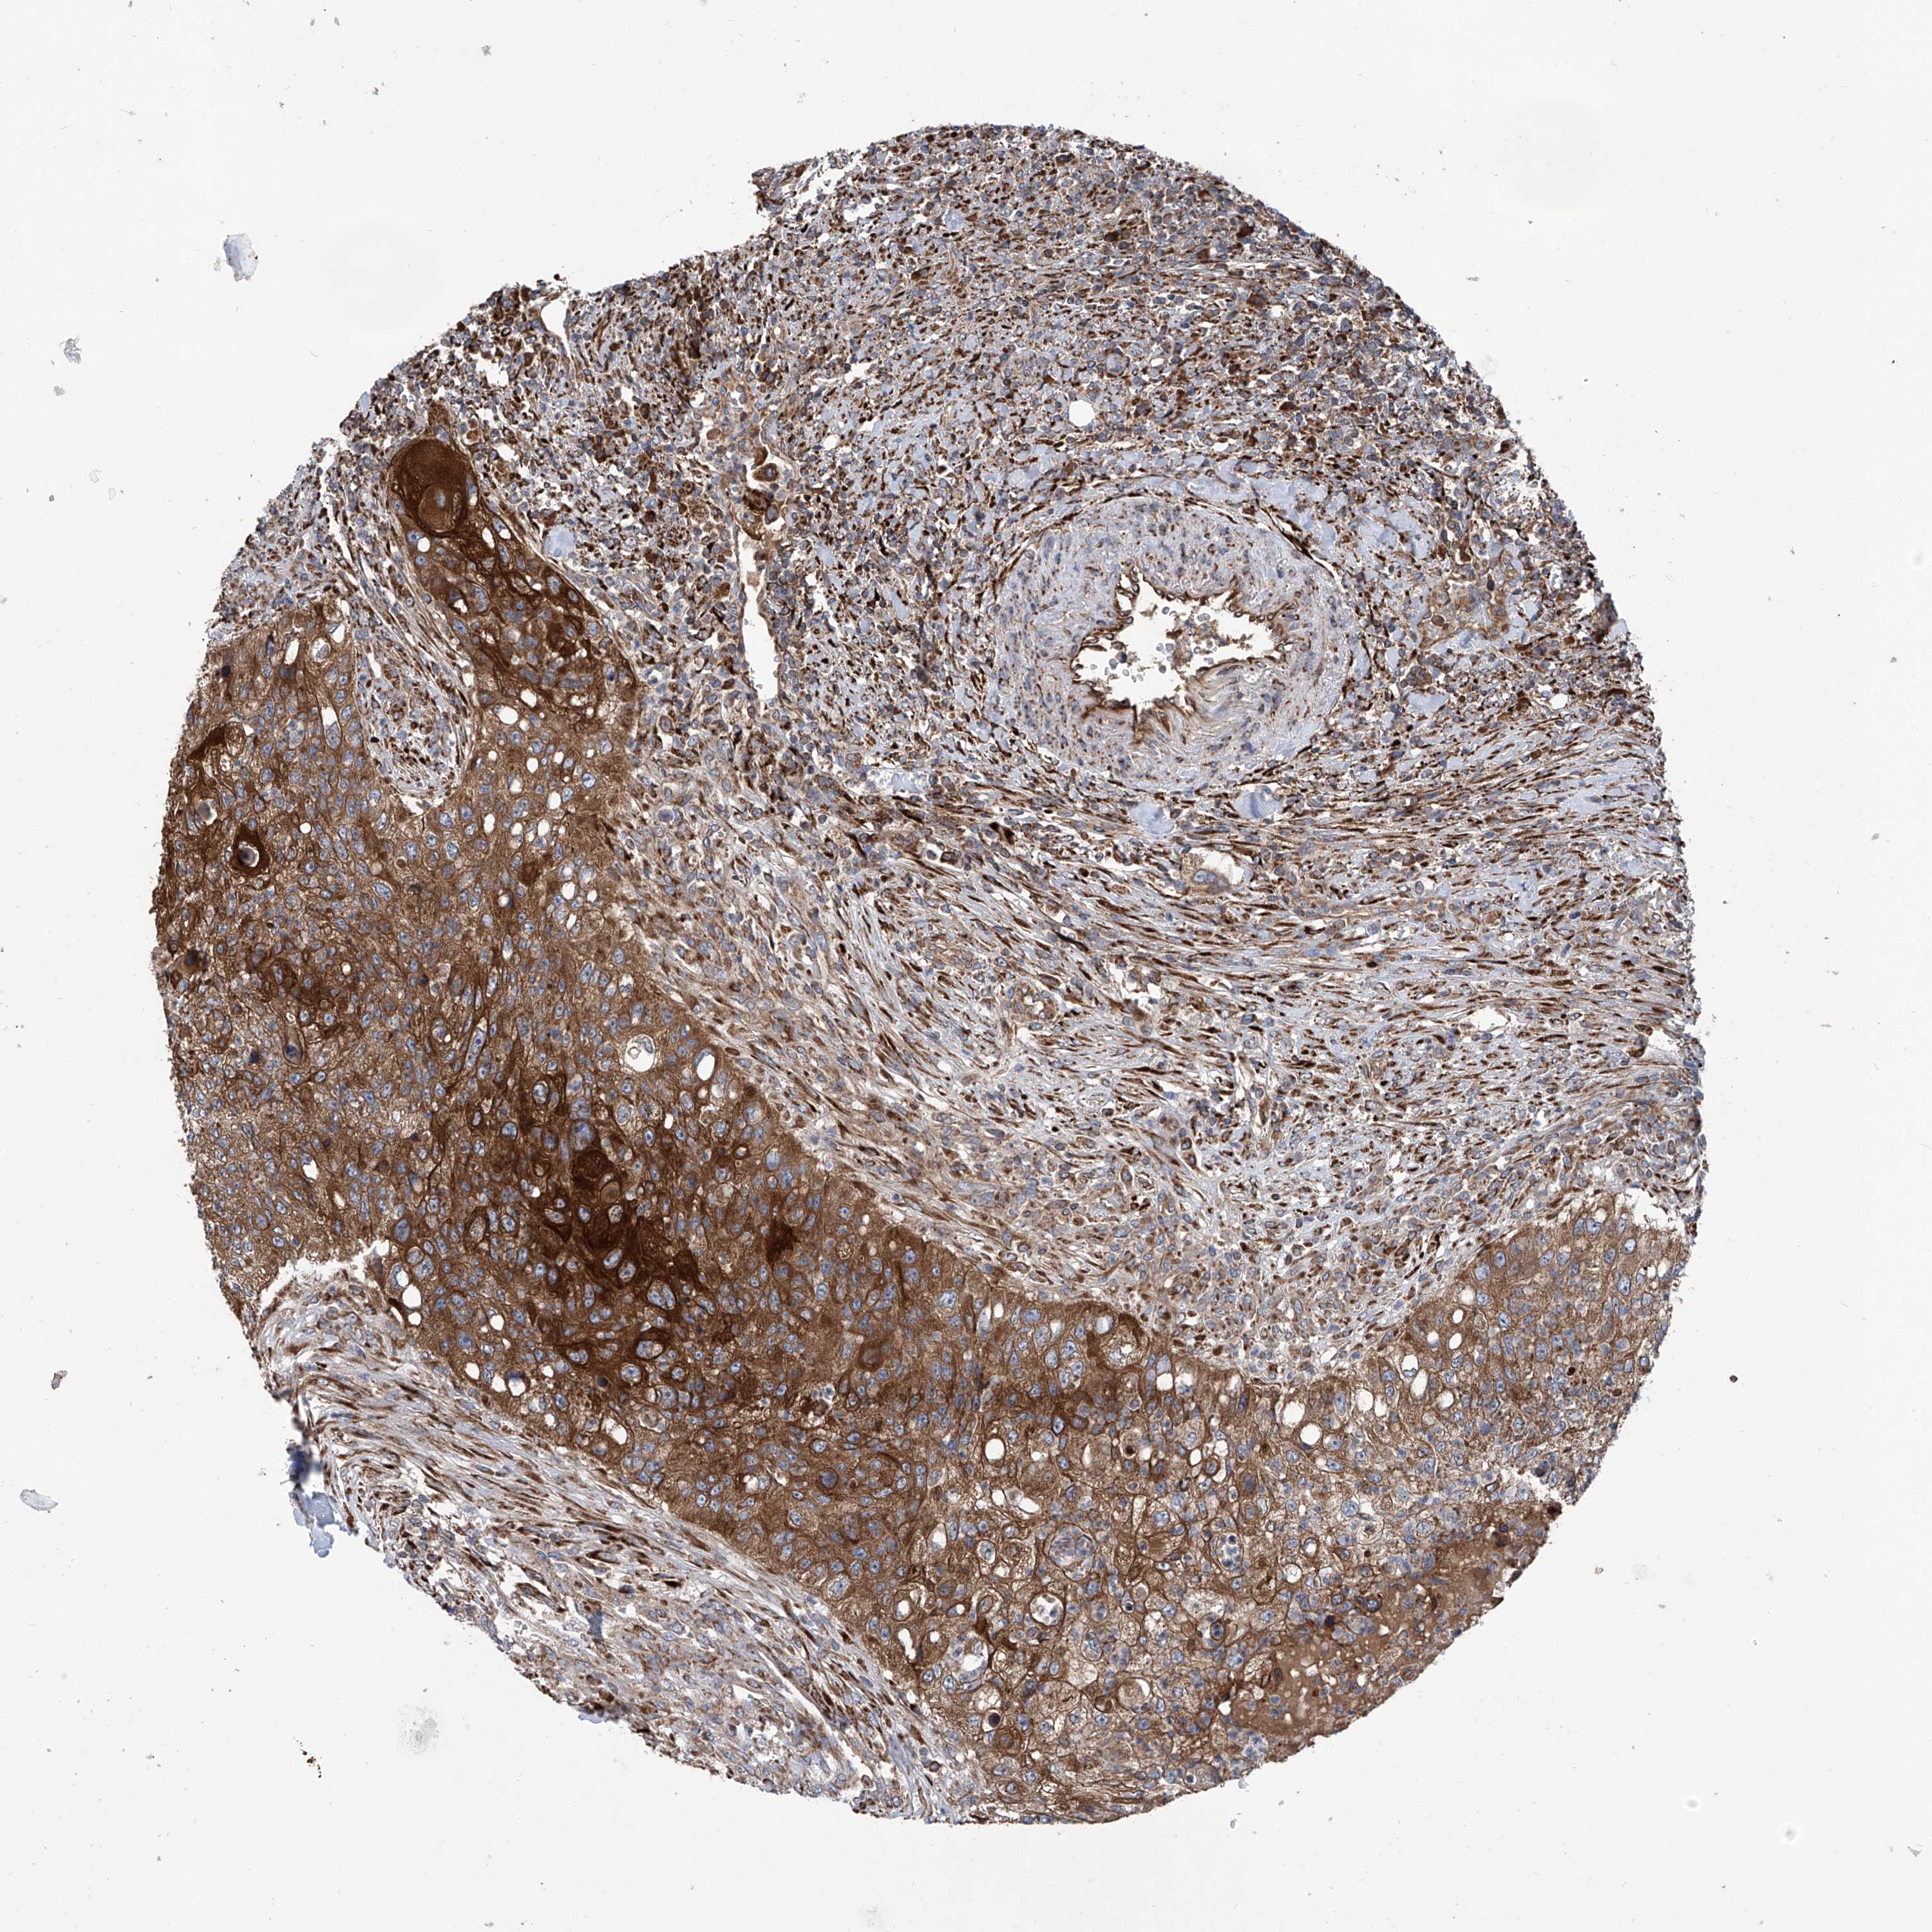

UROTHELIAL CANCER - Protein expressioni

A mouse-over function shows sample information and annotation data. Click on an image to view it in a full screen mode. Samples can be filtered based on level of antibody staining by selecting one or several of the following categories: high, medium, low and not detected. The assay and annotation is described here.

Note that samples used for immunohistochemistry by the Human Protein Atlas do not correspond to samples in the TCGA dataset.

Antibody stainingi

Antibody staining in the annotated cell types in the current human tissue is reported as not detected, low, medium, or high, based on conventional immunohistochemistry profiling in selected tissues. This score is based on the combination of the staining intensity and fraction of stained cells.

Each image is clickable and will lead to virtual microscopy that enables deeper exploration of all samples and also displays staining intensity scores, fraction scores and subcellular localization as well as patient and tissue information for each sample.

Antibody HPA031608

Antibody HPA031609

Antibody HPA031610

Staining

High

Medium

Low

Not detected

Intensity

Strong

Moderate

Weak

Negative

Quantity

>75%

75%-25%

<25%

None

Location

Nuclear

Cytoplasmic/membranous

Cytoplasmic/membranous,nuclear

Urothelial carcinoma, Low grade

Urothelial carcinoma, High grade